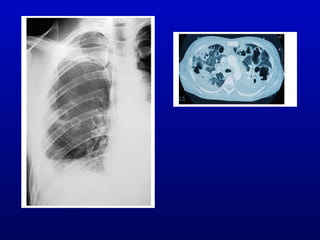

Pathologic Changes

• Septic or bland pulmonary embolism

• Chest X-ray

– Septic emboli in right-sided IE

– Valve calcification

– CHF